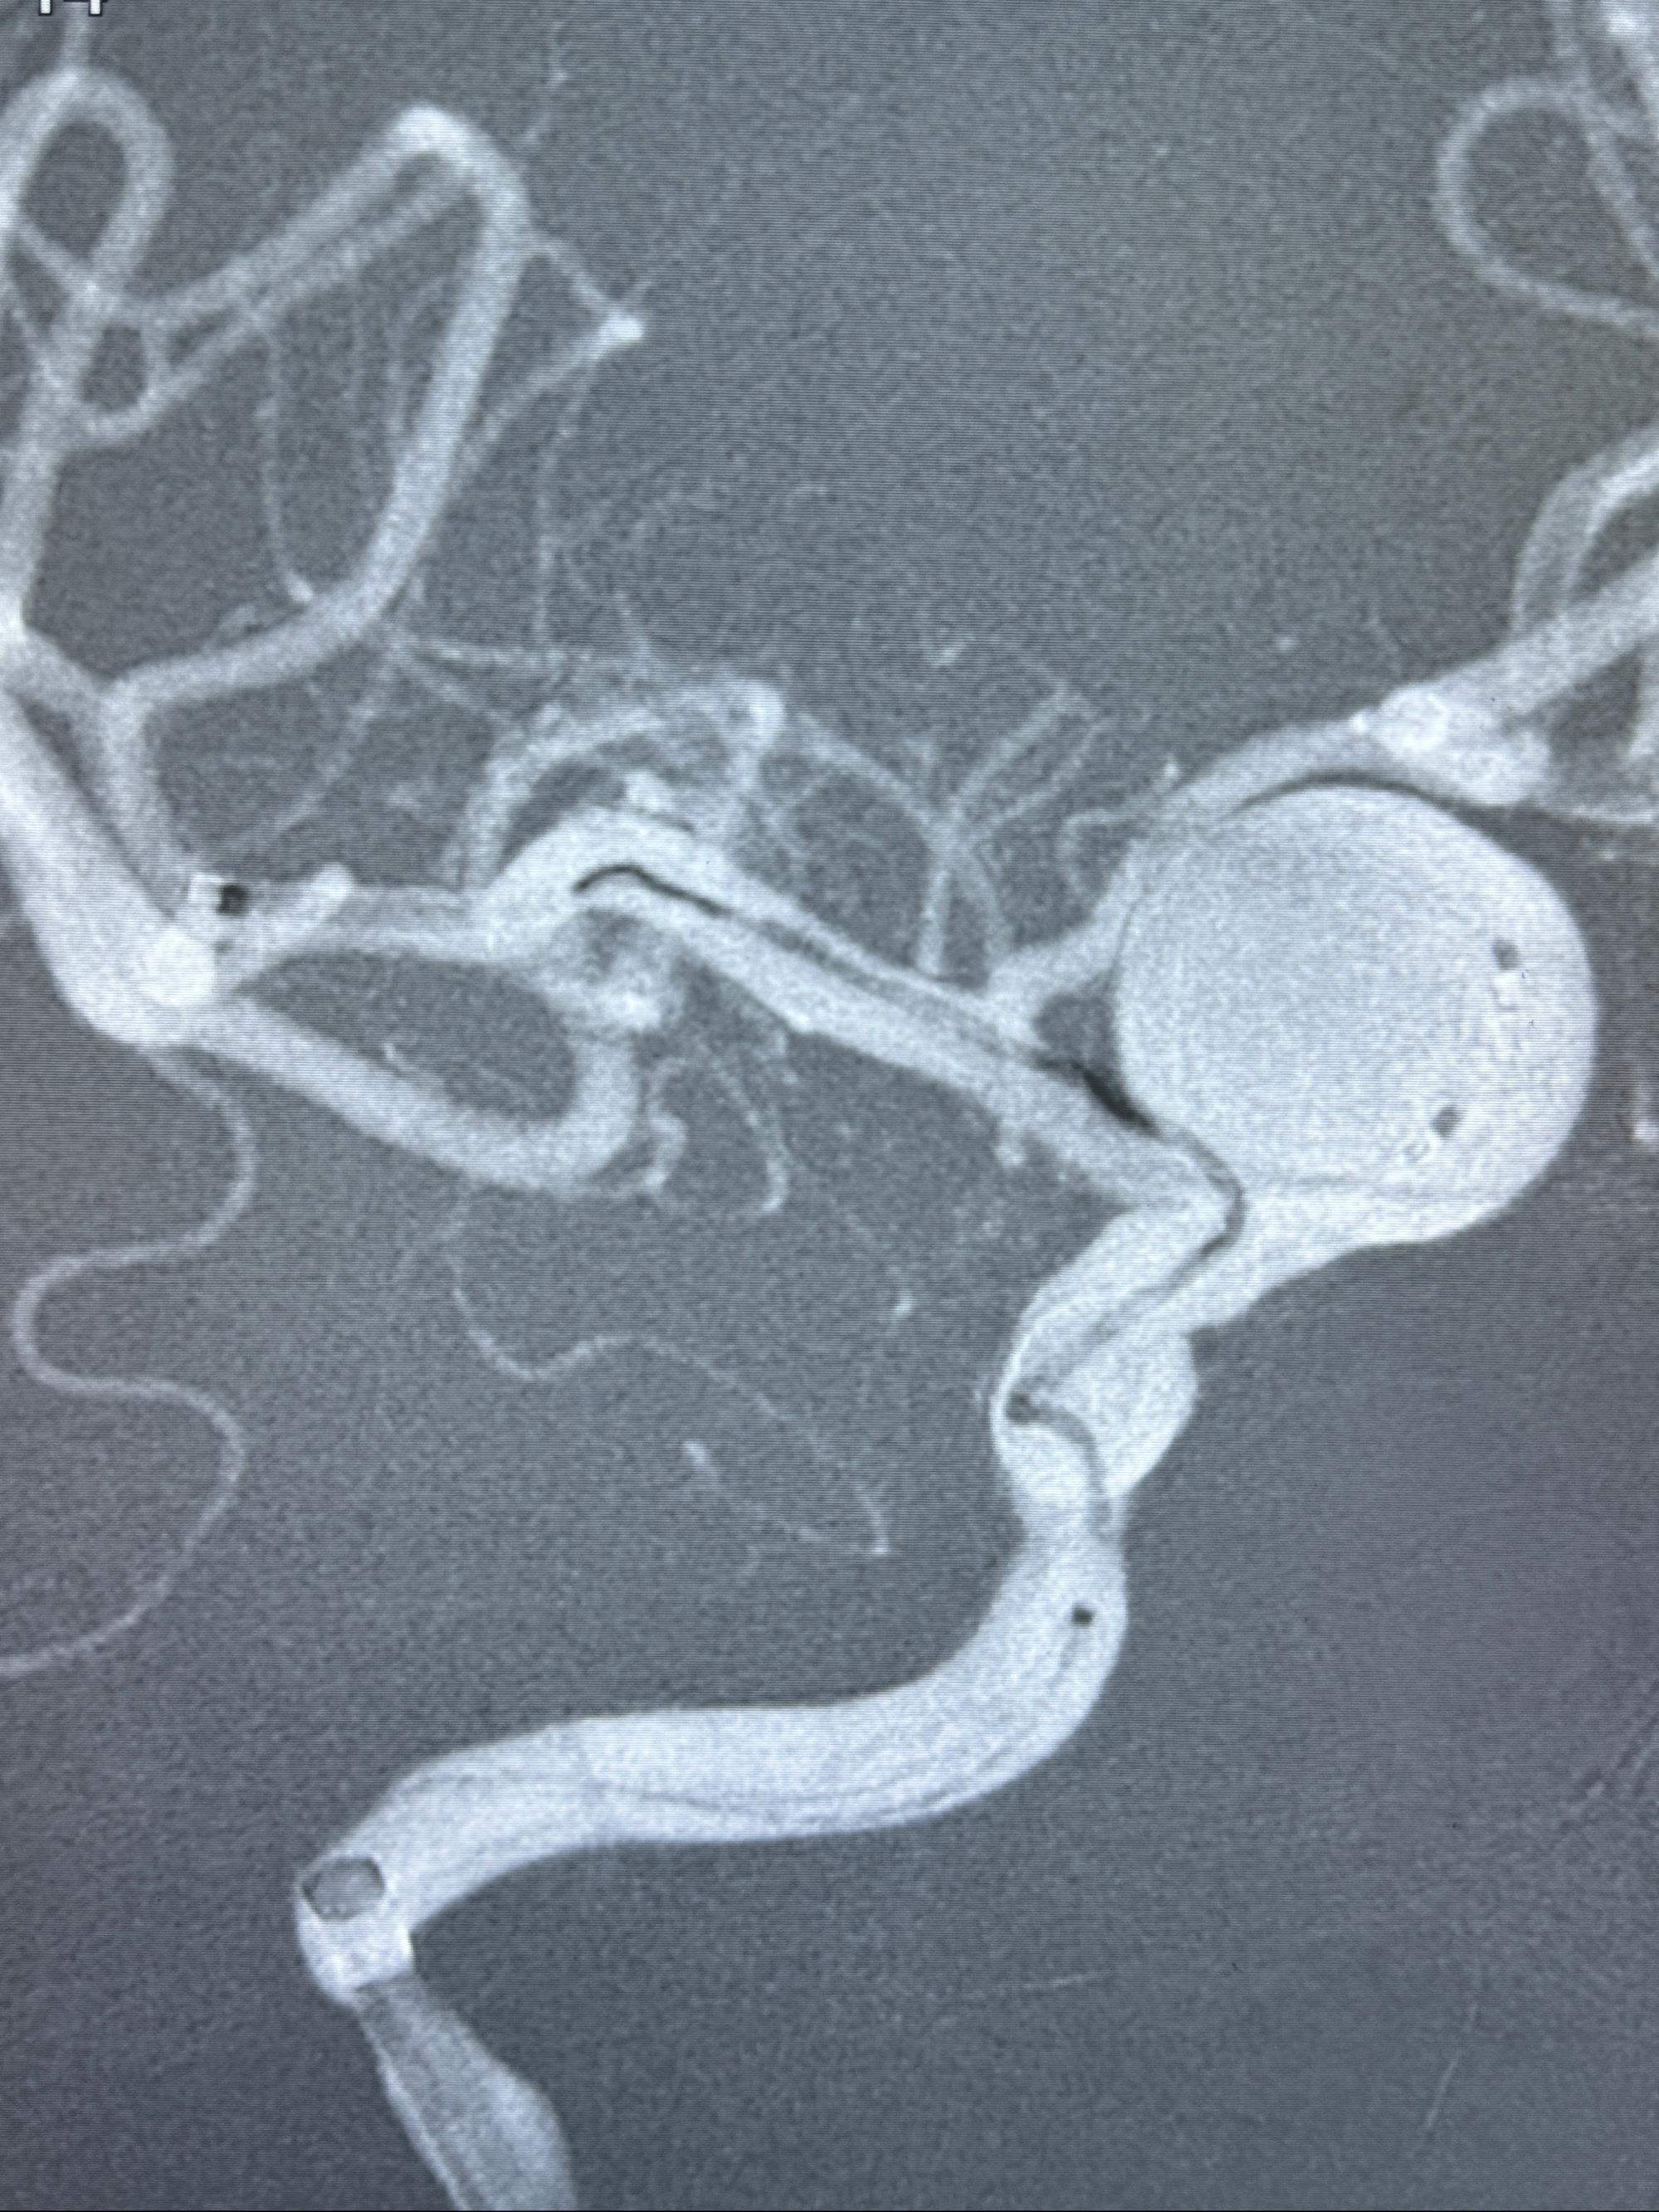

现病史:患者诉2年来反复发作性头痛,顶枕部为主,因自己考虑高血压可能,未予系统检查;患者约20日前无明显诱因下突发剧烈头晕,有天旋地转感,不能睁眼,伴视物模糊;外院查头颅MRI+MRA提示:左侧颈内动脉C6段动脉瘤;遂至复旦大学附属华山医院就诊,于2023-12-08行全脑血管造影提示:右侧颈内动脉C6段动脉瘤,瘤颈6.68mm,动脉瘤大小13.28*12.34mm,建议行密网支架辅助栓塞术治疗,因缺乏相关材料遂出院。现患者仍有顶枕部头痛不适,为求进一步诊疗脑血管病变至我科就诊,收治入院。

2023-12-08 复旦大学附属华山医院 全脑血管造影:右侧颈内动脉C6段动脉瘤,瘤颈6.68mm,动脉瘤大小13.28*12.34mm

2023-12-08外院DSA:右侧颈眼动脉瘤,约13*12mm大小,压颈试验显示左右向及后向前代偿可

测量动脉瘤的大小:16*13.8*7.6mm大小,较原先变大,考虑双抗后瘤内血栓溶解可能